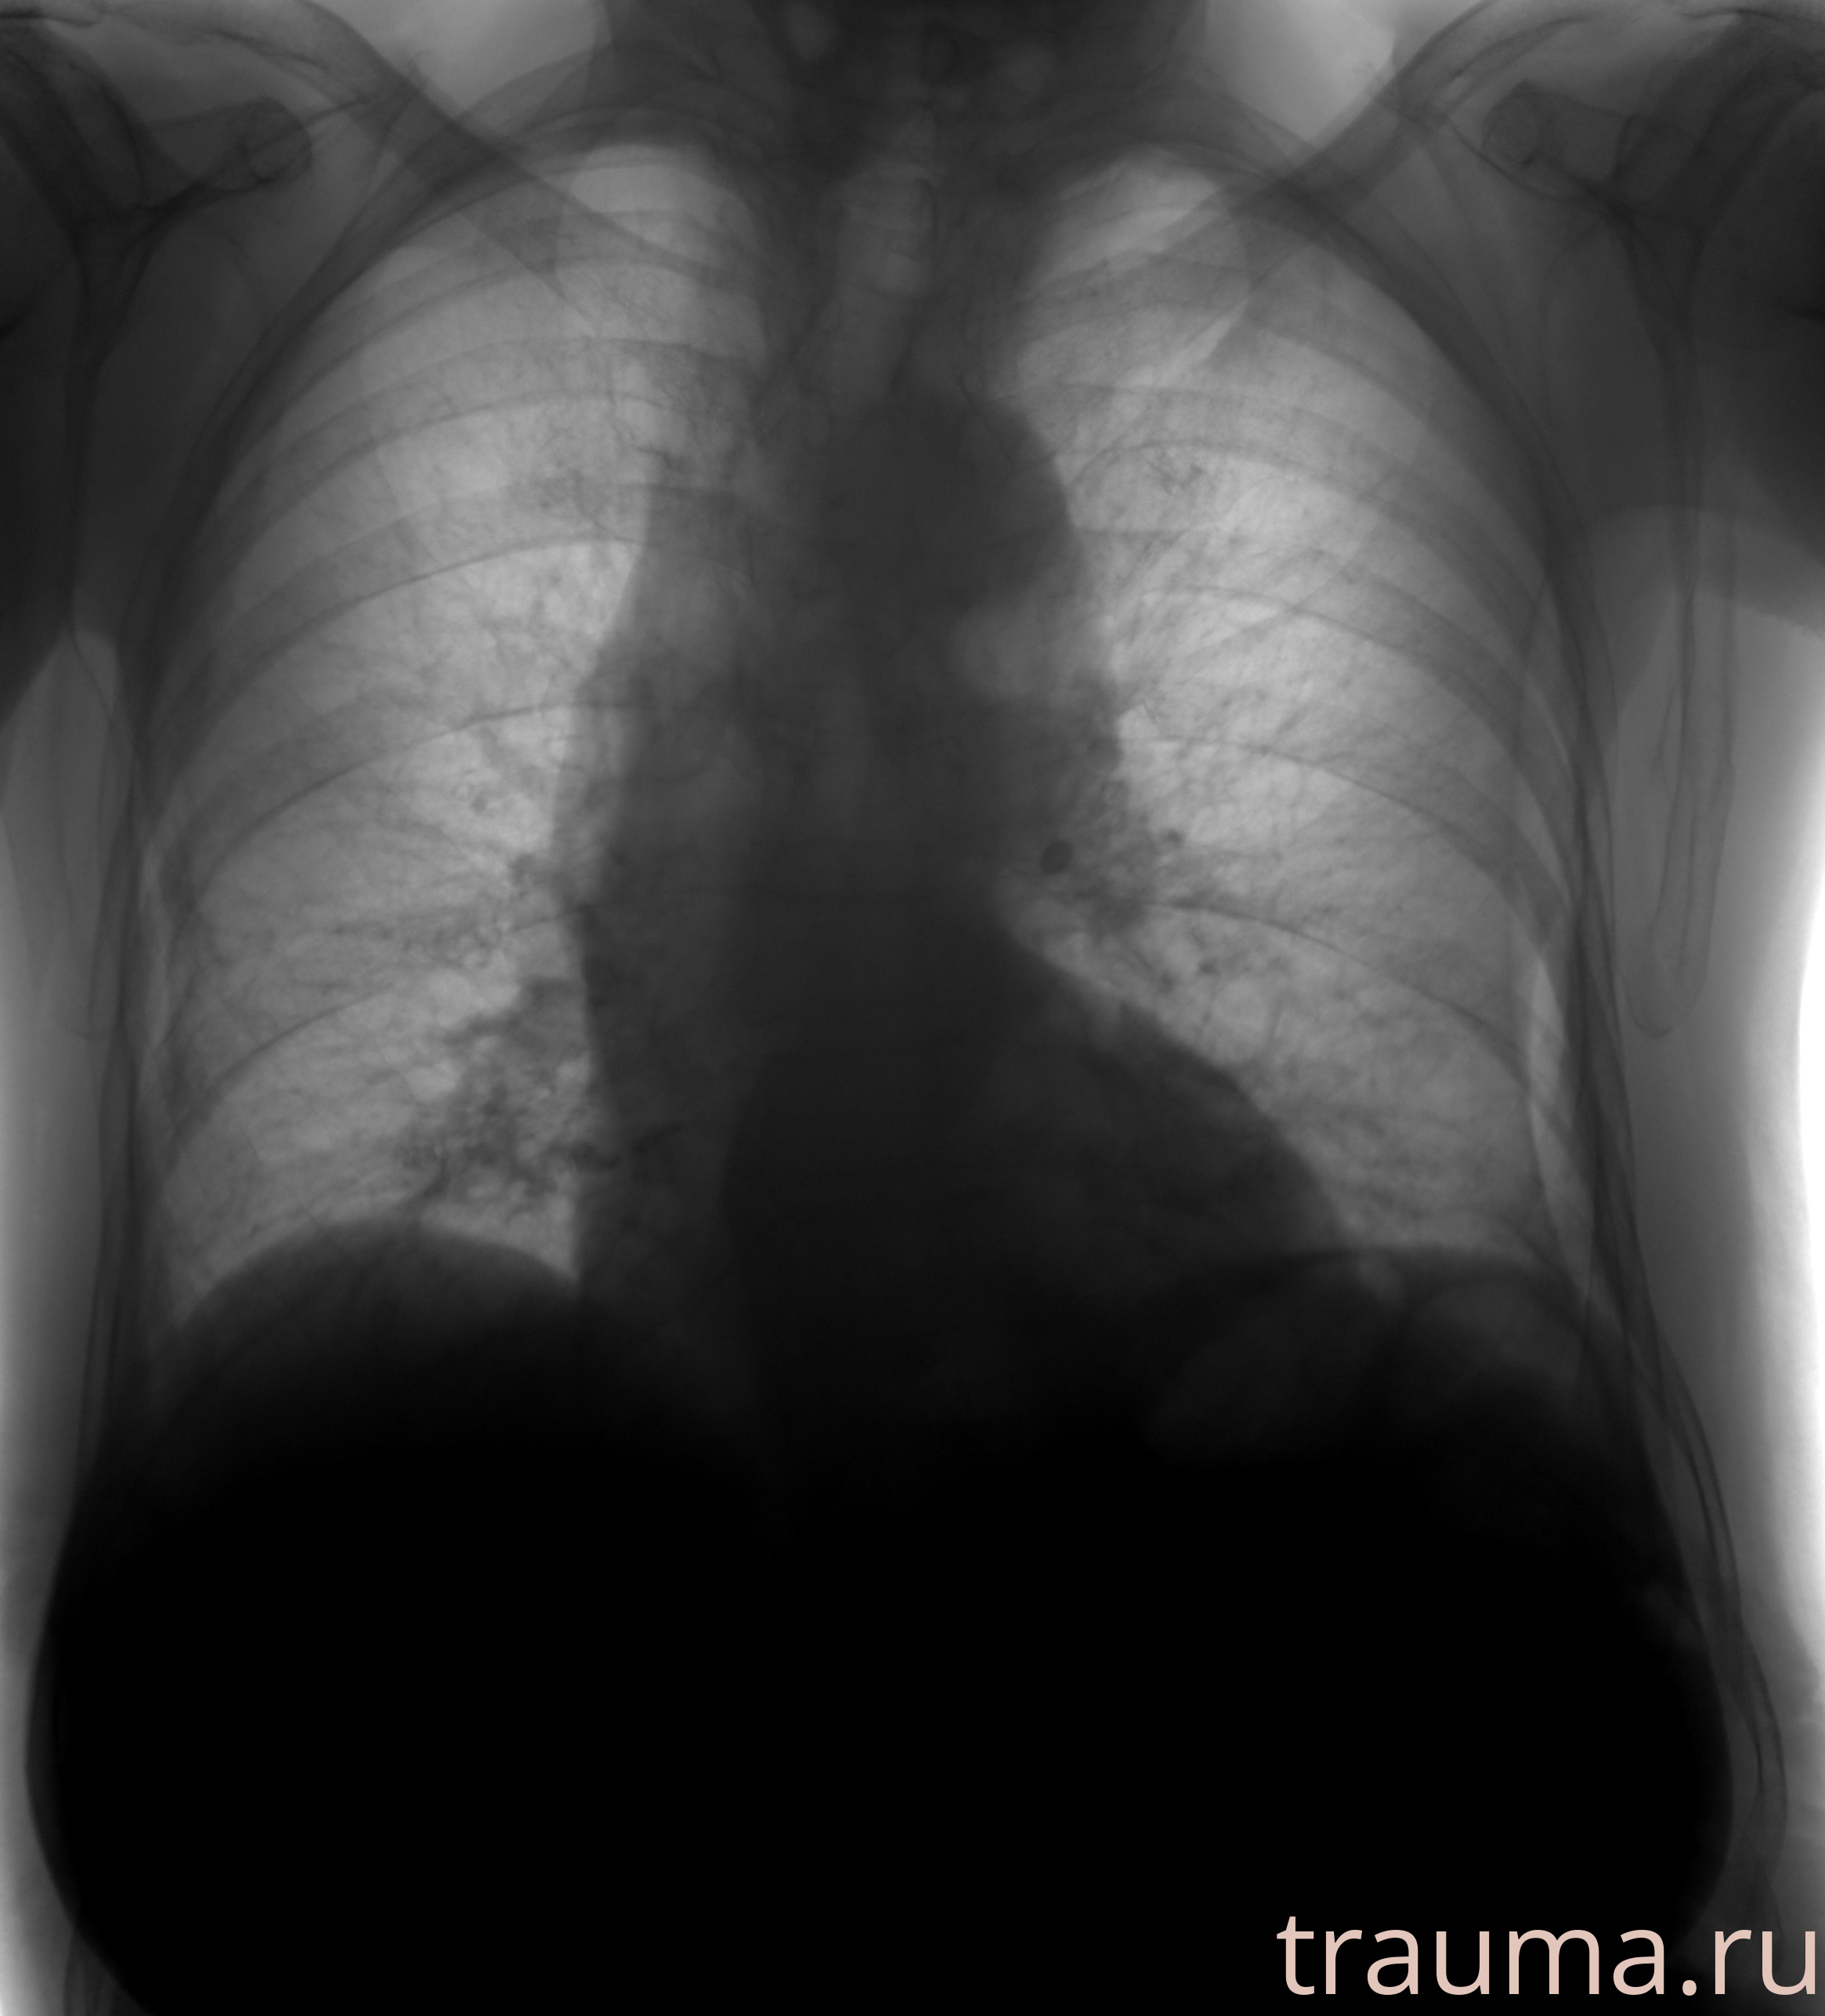

Рентгенограммы

Рентген на дому: по вашему адресу приезжает врач-рентгенолог, травматолог-ортопед с мобильным рентгеновским аппаратом, проводит диагностику травмы или заболевания, делает необходимые рентгенограммы, дает рекомендации по дальнейшему лечению. Получить качественные снимки в домашних условиях возможно благодаря уникальной методике, разработанной МосРентген Центром для института  Склифосовского

при переломе шейки бедра и пневмонии от компании МосРентген Центр - партнера Института имени Склифосовского